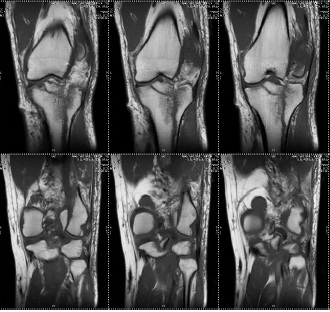

A 26 y-old male sustained a Type IIc Fraser and Type IVb Agarwal and Singh Floating knee injury on the right side. This included displaced intra-articular fractures of the lateral femoral condyle and lateral tibial plateau, a displaced patellar fracture with Grade II ACL tear and PCL sprain, complex tear of the lateral meniscus, and extensor mechanism rupture. Treatment involved external fixation for ipsilateral shaft fractures of the femur and tibia, along with a physiotherapy rehabilitation protocol for associated soft tissue injuries and tension band wiring for the patellar fracture. The patient achieved a good functional outcome after 2 y of follow-up, as depicted in [fig. 1a-d].

Fig. 1c: Preoperative MRI coronal and saggital view showing displaced intra-articular fracture of lateral femoral condyle and lateral tibial plateau with displaced fracture of patella with Grade II ACL tear and PCL sprain and complex tear of lateral meniscus and extensor mechanism rupture